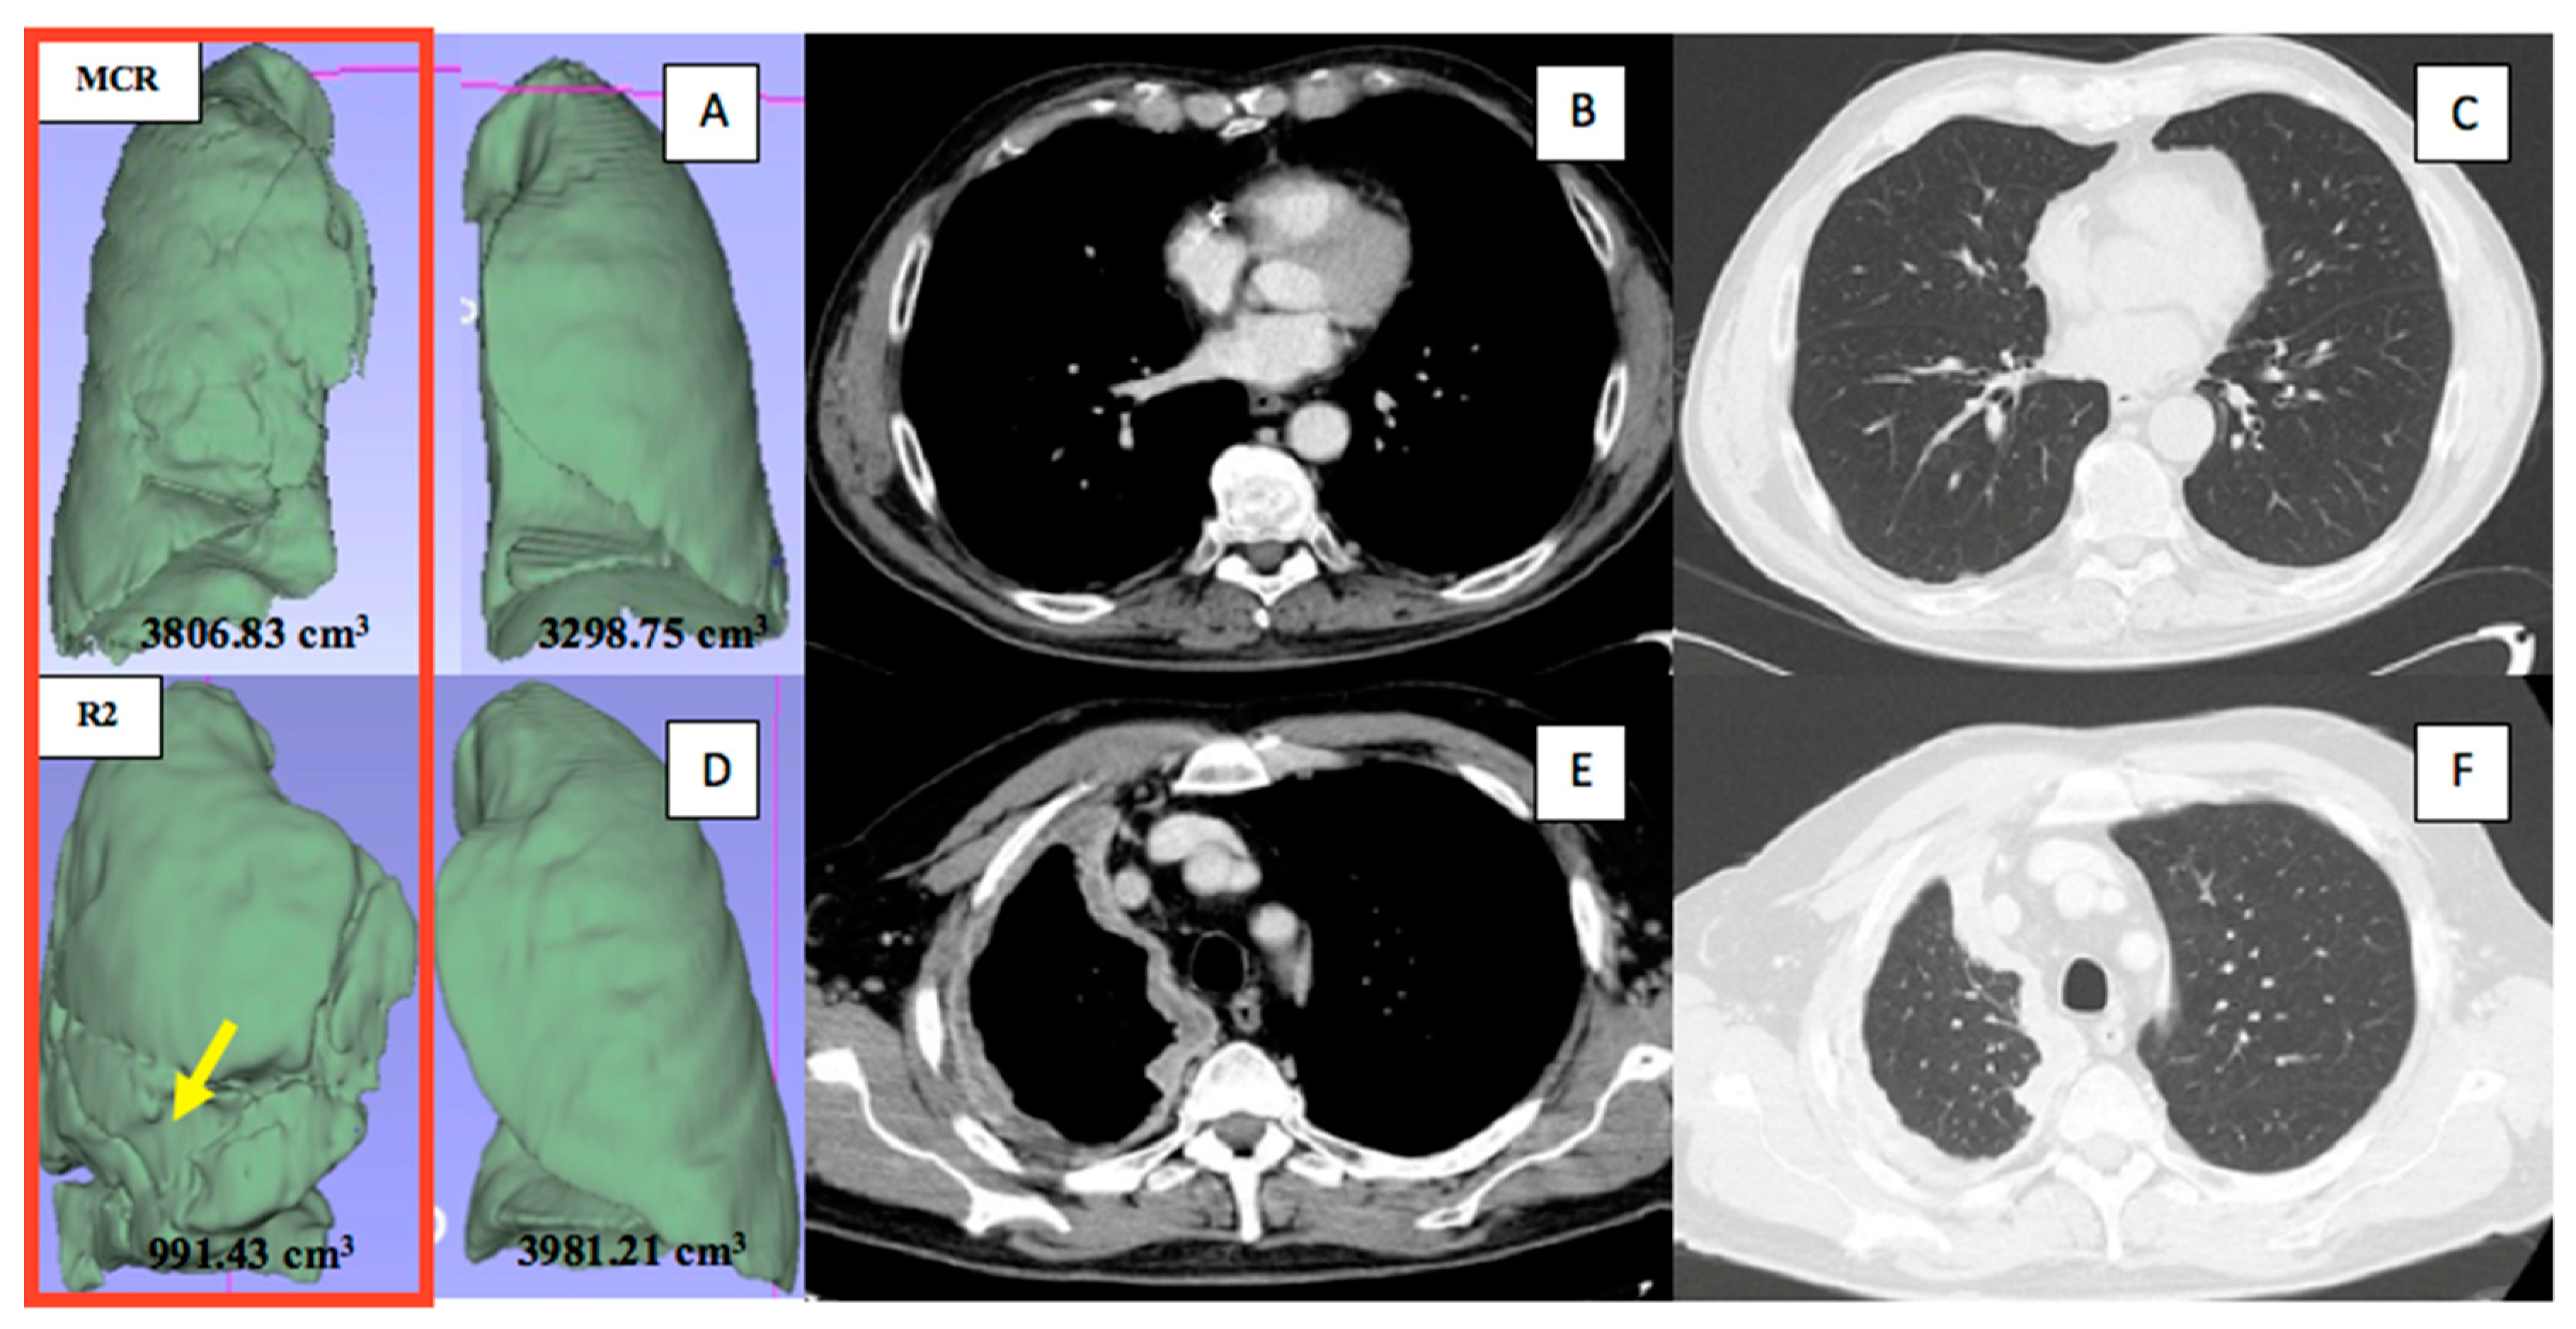

| Ipsilateral pathological lung volume (cm3), median (IQR) | 1944 (1528–2352) | 1545 (1322–1782) | 0.03 |

| Difference in contralateral and ipsilateral lung volume (cm3), median (IQR) | 677.2 (217.4–1252) | 1371 (667.4–2164) | 0.02 |

| Difference in contralateral and ipsilateral lung volume (%), median (IQR) | 25.28 (7.4–41.73) | 47.01 (28.39–59.01) | 0.01 |

| 8 | M | Right | DCWI | 72 | 181 | 991.43 | 75.10 |